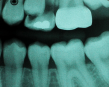

A 7-year-old boy had a newly erupted mandibular right permanent first molar. The tooth had hypoplastic and hypocalcification malformation and associated dental caries (Figure 14). After inferior alveolar block anesthetic injection, the rubber dam was applied using the slit-dam method.8 Occlusal-distobuccal preparation was completed using a water-cooled, coarse-grit cylindrical diamond bur. All carious and chalky hypocalcified tooth structure was removed. Preparation design included mechanical undercut retention form (Figure 15).  After placement of an orthodontic band as a matrix, without removal of the rubber dam clamp, 5% glutaraldehyde/HEMA desensitizing solution was applied and agitated with a microbrush for two 60-second exposures, and air-dried after each application (Figure 16). A self-etching bonding agent was then painted over the enamel and dentin and spread to a thin layer with the air syringe. After 10 seconds of light exposure, an RMGI bioactive ionic resin-based composite was injected to overfill, in one portion. The restoration was trimmed with slow-speed diamond burs, and the self-etching bonding agent was applied over the composite surfaces and surrounding enamel. The light beam was applied for another 10 seconds (Figure 17).  Occlusion was determined using articulating paper, and corrections were made (Figure 18). The occlusal view of the restored molar is shown 20 months after treatment (Figure 19).

A 7-year-old presented with a malformed, sensitive molar.

Figure 14

The tooth was prepared for a restoration with an RMGI bioactive ionic resin-based composite.

Figure 15